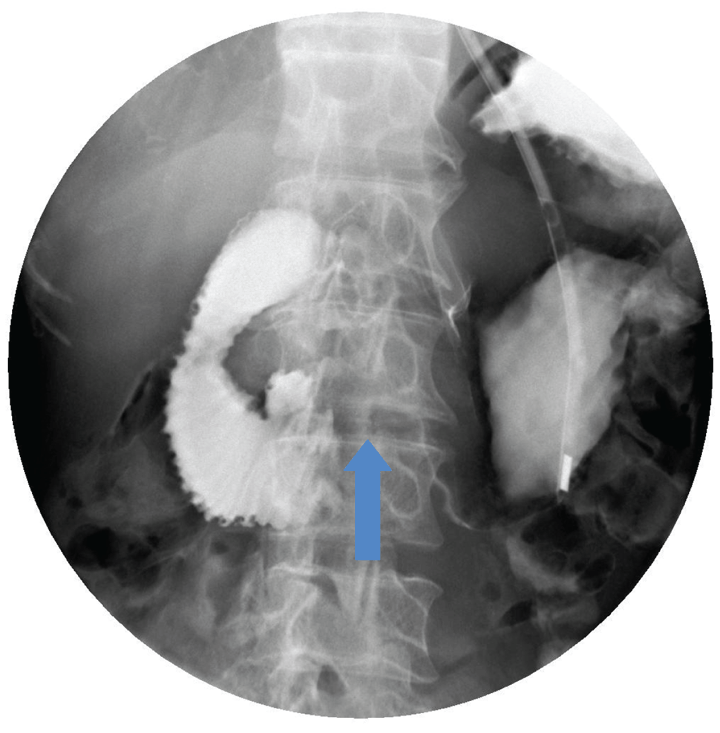

A 64-year-old schizophrenic elderly male was admitted in Singapore government hospital for epigastric pain of 1 day duration associated with a two-day history of vomiting. The character of the vomitus was uncertain. He had lost 30–40 kg of weight over several months. The patient denied postprandial pain and had no previous similar episode. He had no past history of surgery and was not on any psychiatric medication. The patient had paranoid schizophrenia but was never compliant with medications. He lived alone and had persecutory thoughts. He was suspicious of people around him and barred all windows and rooms. He also mentioned cameras watching him and “people” want to harm him. He refused to go out and consumed mainly instant noodles for several years. One month before this admission, he was admitted for hypoglycemia secondary to poor oral intake and incidentally had low calcium and vitamin D deficiency. His vital signs were stable on admission. He appeared comfortable but was severely cachectic with a body mass index of 10.9 kg/m2 (weight 34.4 kg, height 178 cm). The abdomen was scaphoid, distended and tender over epigastric area with no sign of peritoneal irritation and succussion splash was positive. Per rectal examination was unremarkable. Initial laboratory studies were largely unremarkable besides the elevated total white, low creatinine and urea. Supine and erect plain abdominal radiograph showed a grossly distended stomach and collapsed bowel distally. (Figure 1) In view of the distended abdomen, positive succession splash and dilated stomach on abdominal radiograph, our initial impression was gastric outlet obstruction. Patient was kept nil by mouth and nasogastric tube was inserted to maintain gastric and duodenal decompression. Nasogastric tube immediately aspirated 2.2 liters of bilious fluid. Upper gastrointestinal series showed distended stomach and duodenum to the level of mid third part, where an abrupt cut-off occurred. (Figure 2) To determine the aetiology, contrast-enhanced computed tomography (CT) scan of the abdomen was arranged and the third portion of the duodenum was clearly ‘pinched’ by the abdominal aorta and the superior mesenteric artery. The aorta-SMA angle was 4 degrees and the aortomesenteric distance measured 5.6 mm. (Figure 3) (Figure 4) In addition, CT scan also revealed obvious reduction of the intra-abdominal fat. There was no free intraperitoneal air. Based on the history, examination and imaging findings, we diagnosed SMA syndrome. Endoscopic guided insertion of nasojejunal tube was performed for enteral feeding as patient was unable to tolerate any oral intake due to duodenal obstruction. (Figure 5) However, the patient was not cooperative with nasojejunal tube feeding. Subsequently, he developed hypoglycemia, hypokalemia and hypotension that was refractory to resuscitation. Consciousness deteriorated and the patient passed away. | ||||||

Superior mesenteric artery syndrome was first described by Austrian Professor Carl Freiherr Von Rokitansky in 1861. [3] Later Wilkie published the first comprehensive case series of 75 patients with what he initially called “duodenal ileus”, 64 of who underwent duodenojejunostomy. Wilkie’s detailed anatomical, clinical and pathophysiological description of extrinsic compression of third portion of duodenum by the superior mesenteric artery has become a common eponym for SMA syndrome. [4] Subsequently, a variety of other names have been used such as chronic cast syndrome and arteriomesenteric duodenal compression syndrome. [5] [6] Superior mesenteric artery originates acutely from the abdominal aorta behind the neck of the pancreas at the level of first lumbar vertebra and travels caudally into the root of mesentery. The transverse portion of the duodenum crosses anterior to the third lumbar vertebra and was separated from the superior mesenteric artery by the retroperitoneal fatty tissue. The normal angle between abdominal aorta and the superior mesenteric artery is 25–60° and the aortomesenteric distance is around 10–28 mm. [7] [8] Such relationship correlates with body mass index. [2] Pathophysiological loss of retroperitoneal and paraduodenal fats can result in aortomesenteric distance less than 8 mm and aorto-SMA angle of 22° or less, resulting in duodenal ‘clamping’. Such pathophysiology can be seen in chronic wasting disease, catabolic state, anorexia and malabsorption. Surgical interventions can occasionally alter the anatomical relationship, jeopardizing the aortomesenteric angle and resulting in SMA syndrome (e.g., scoliosis surgery, aortic aneurysm repair, bariatric surgery). [1] [5] The SMA syndrome can present acutely or chronically with signs and symptoms of proximal gastrointestinal tract obstruction (i.e., nausea, vomiting, weight loss, sense of repletion and postprandial abdominal distension). Such presentations, however, are nonspecific to SMA syndrome and diagnosis is frequently delayed. Henceforth, a high index of suspicion is required and a comprehensive investigation is recommended to rule other conditions that are common and has different treatment implication including pancreatitis and peptic ulcer disease. [9] Upper gastrointestinal series, contrast-enhanced computed tomography (CT) scan, magnetic resonance angiography (MRA), ultrasound (US) and endoscopy are modalities that can be utilized to establish diagnosis. Our patient had upper gastrointestinal series that revealed a classical dilated proximal duodenum with abrupt contrast cut-off at the transverse portion of duodenum. Computed tomography scan of abdomen with contrast can clearly demonstrate the obstruction site, determine the aetiology of the obstruction and allows evaluation of aortomesenteric angle and aortomesenteric distance, both of which are sensitive measures of diagnosis. An aortosuperior mesenteric artery angle of less than 25° and aortomesenteric distance less than 8 mm are highly suggestive of SMA syndrome. [9] In our patients, both parameters were reduced with angle and distance of 4° and 5.6 mm, respectively. Upper endoscopy can be used to rule out stenosing lesions in the duodenum. With the advent of noninvasive radiological studies, conventional arteriography is rarely needed in the workup of SMA syndrome except in cases where diagnosis is not clear. The treatment of SMA syndrome can be either conservative or surgical. Patients with SMA syndrome initially require nasogastric tube insertion for gastrointestinal decompression, fluid resuscitation, correction of electrolyte abnormalities and early nutritional support. Nutritional support aims to promote body weight gain and restore the retroperitoneal fat tissue with subsequent increase in aortomesenteric angle and reduction in duodenal obstruction. Nasojejunal tube that is placed distal to the obstruction allows enteral administration of nutrition. Parenteral nutrition may be an alternative but it is not without its associated complications. Notably, patient should be monitored for refeeding syndrome during nutritional rehabilitation as these patients are malnourished and are susceptible to electrolyte and fluid shifts. Duration to achieve symptomatic improvement is variable in conservative nutritional treatment and has been documented to range from 2–169 days. [1] Patients with shorter history of SMA syndrome have higher success rate with conservative management. On the other hand, those with more chronic history have a prolonged hospital stay with low success rates of conservative treatment alone and surgery after a period of refeeding and weight gain is indicated. [8] Several surgical options have been proposed to resolve or bypass the duodenal compression including Strong’s procedure (caudal mobilization of duodenojejunal flexure by division of ligament of Treitz), gastrojejunostomy and duodenojejunostomy. The advantage of Strong’s procedure includes maintaining bowel integrity, easier and quicker to perform and less invasive and is a safer procedure. [9] However, Strong’s procedure has high failure rate of 25% and presumably due to difficulty in mobilizing the duodenum with interference from intra-abdominal adhesions and the short vessels of the inferior pancreaticoduodenal artery. Gastrojejunostomy can decompress the stomach adequately but it does not resolve the duodenal obstruction and the patient can have persistent symptoms. Furthermore, such bypass operation can cause blind loop syndrome, gastric bile reflux and peptic ulceration that necessitate second operation (i.e., duodenojejunostomy). Duodenojejunostomy is the surgical treatment of choice and can be performed with or without division of fourth portion of the duodenum. It has a reported a success rate of 90%. [10] | ||||||